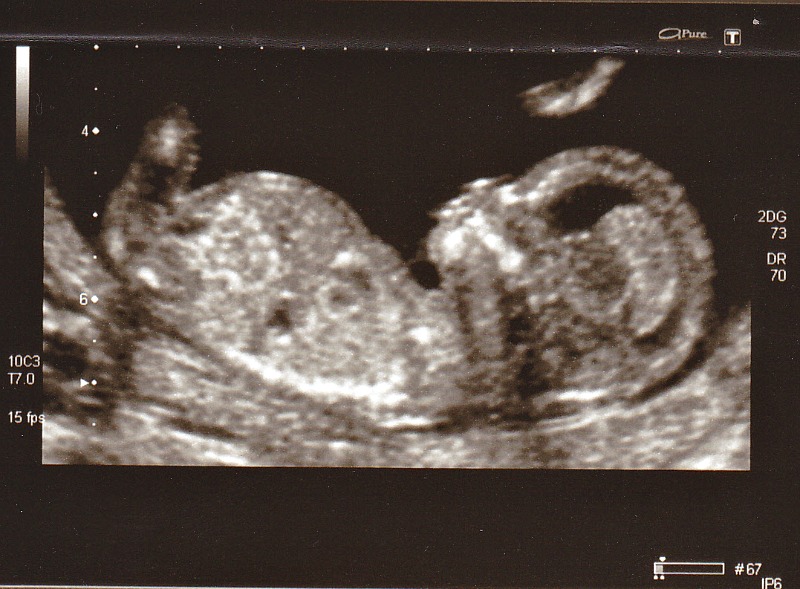

| The thirteen week scan |

| Daisy on the inside |